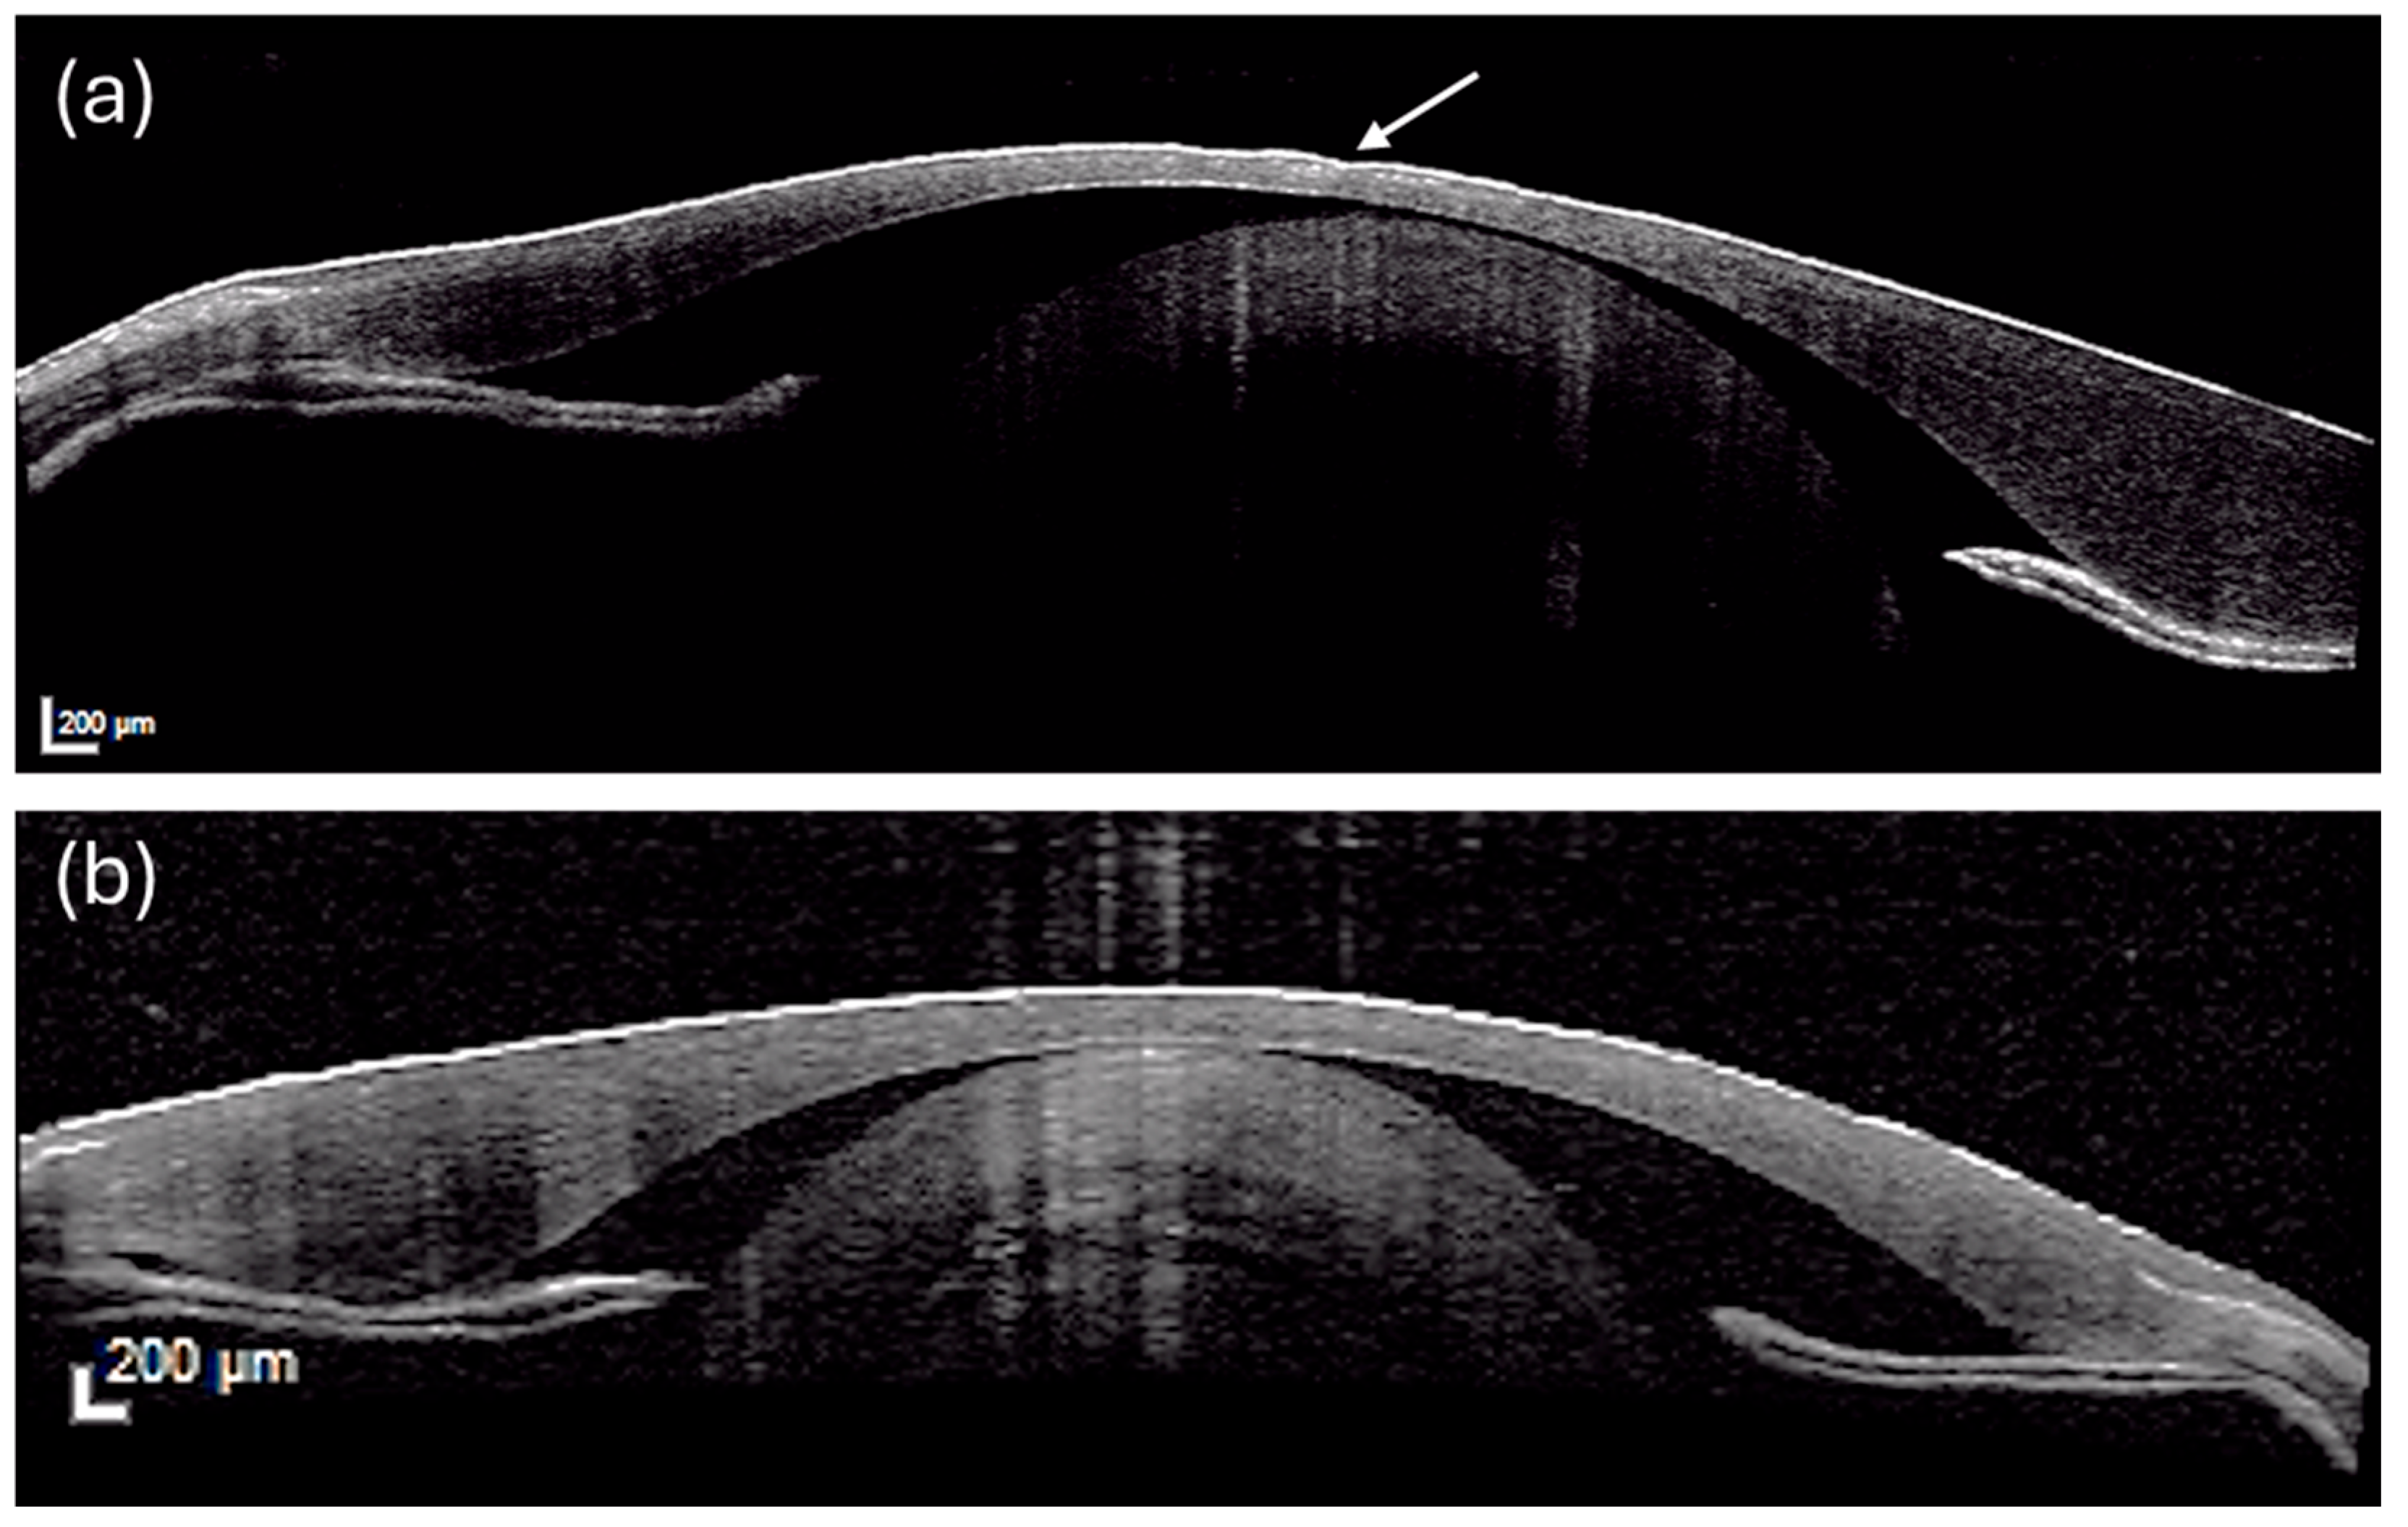

13] and have been traditionally evaluated through histopathological examination. More recently, Optical Coherence Tomography (OCT) has emerged as a non-destructive, high-resolution imaging technology tool that enables detailed in vivo or ex vivo evaluation of corneal morphology, allowing the detection of subtle alterations, including epithelial thinning or loss, and stromal disorganization that may not be readily evident at gross examination. Although its application in fish research is still limited, OCT has been successfully used to investigate ocular structures in different fish species (zebrafish

15]), supporting its potential as a non-destructive technique for the detection of ocular damage.

2.5. Imaging: Optical Coherence Tomography

OCT was performed on eyes (N = 8/tanks, N = 56 in total) previously fixed in 10% buffered formalin and subsequently washed in phosphate-buffered saline (PBS). Before imaging, each eye was positioned to allow optimal alignment with the OCT scanning beam. Corneal structures were visualized using a corneal lens. Following corneal imaging, the globe was carefully opened to expose the posterior chamber, allowing direct visualization of the retina. All OCT examinations were conducted under standardized conditions to ensure consistency among samples.

Despite these differences in water quality, zootechnical parameters did not differ significantly between experimental groups. Growth performance and related indicators remained comparable, suggesting that the 28-day experimental period may not have been sufficient for water quality imbalances to translate into measurable effects at the whole-animal production level. This apparent discrepancy suggests that moderate fluctuations in nitrogenous compounds may not immediately translate into production-level consequences, especially in a species known for tolerance to high stocking densities (up to 100 kg/m

29]. Rather than reflecting the absence of stress, the lack of growth differences likely indicates that sublethal environmental challenges first manifest at the tissue level before impacting whole-animal performance. In this context, ocular tissues, particularly the cornea, appeared as a highly responsive indicator of environmental variability. The main advantage of using OCT is the acquisition of microscopic images of the entire unprocessed eye. These images can then be easily correlated with histological findings. On the contrary, fixation can introduce artifacts, and measurements obtained on these samples cannot be translated in vivo as such. However, when comparing tissues that underwent the same fixation process, OCT can provide valuable information. Even if OCT data help assess corneal alterations and provide comprehensive visualization of the cornea, its use in farmed fish is currently restricted to research studies. This limitation stems from the high cost of the instrument and the challenges associated with replicating analyses on the same individual. However, OCT identified epithelial thinning and areas of epithelial loss in the cornea of control fish, indicating compromised ocular surface integrity. Histological examination confirmed these findings: CTR corneas exhibited disepithelialization, whereas PEC corneas largely preserved normal architecture. These morphological changes were further quantified by histomorphometric analysis, which showed significant corneal epithelial thinning in CTR fish versus relative preservation or even thickening in PEC fish. Such epithelial thickening in PEC fish may represent an adaptive, early defensive response aimed at reinforcing barrier function under mild stress conditions. Teleost fish are known for remarkable regenerative capacity in epithelial tissues [